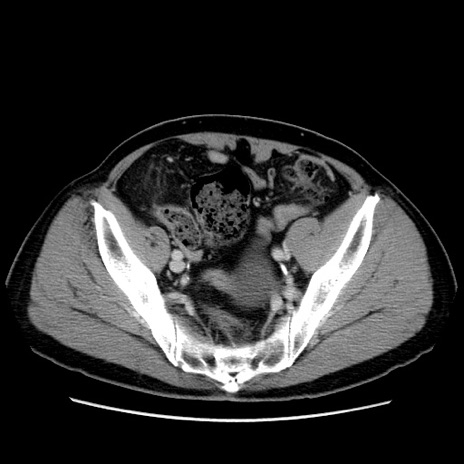

矢状断像